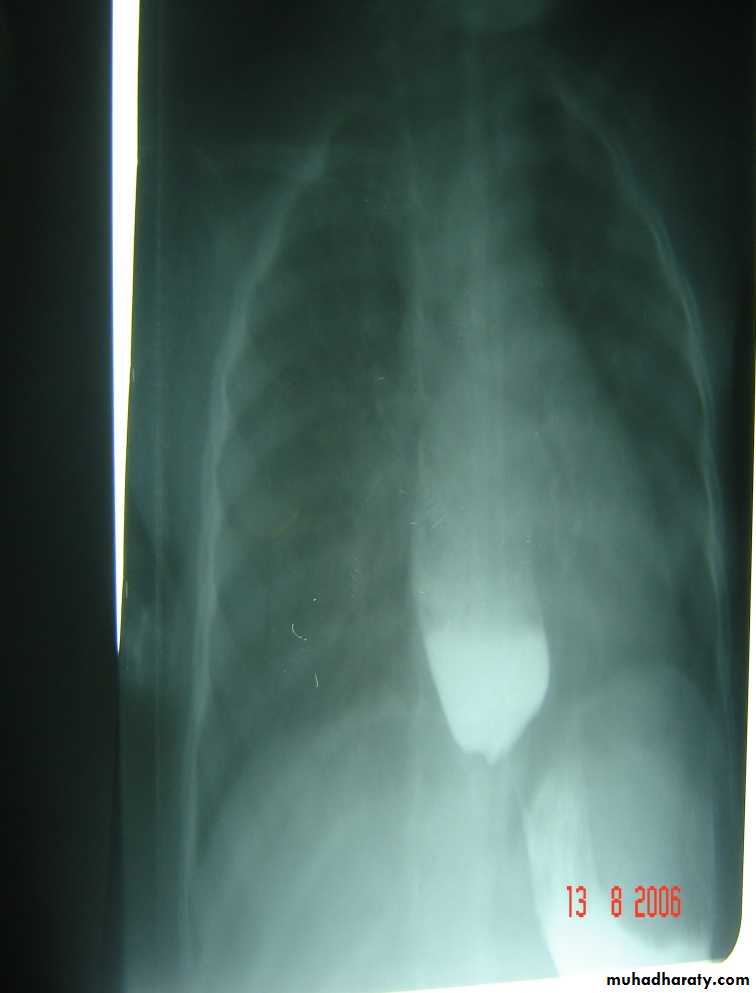

Diagnosis: pyloric stenosis

Presentation:• Projectile vomiting (not present in first two weeks)

• Olive mass in the abdomen

• Positive prestalsis

• FTT

Diagnosis:

• Clinically

• Ultrasound

• Ba-meal dilated stomach – failure to pass to intestine – string sign

Treatment: surgery pyloromyotomy (rami stick surgery)